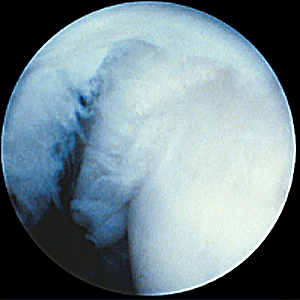

整形外科における手術の役割 肩腱板断裂治療のアルゴリズム 不全断裂 小断裂 中~大断裂 一次修復不能広汎性断裂 保存療法(リハビリ:運動療法/物理療法) 手術療法 関節鏡下腱板修復術 腱移行術、腱移植術、リバース型人工関節 腱板断裂の治療の基本は保存療法ですが、それが反応しない場合には、関節鏡下腱板修復術が適応されます。 修復前 修復後 関節鏡下腱板修復術は「肩に小さな穴を数か所開け、関節鏡で中をのぞきながら縫い合わせる方法」で、私の得意分野です。 不全断裂 小断裂 中~大断裂 一次修復不能広汎性断裂 保存療法(リハビリ:運動療法/物理療法) 手術療法 関節鏡下腱板修復術 腱移行術、腱移植術、リバース型人工関節 縫いきれないほどの大きな断裂には、腱の移植や人工関節が必要になります。 手術を望まない方へは、間葉系幹細胞を用いた再生医療の提供に取り組んでいます。